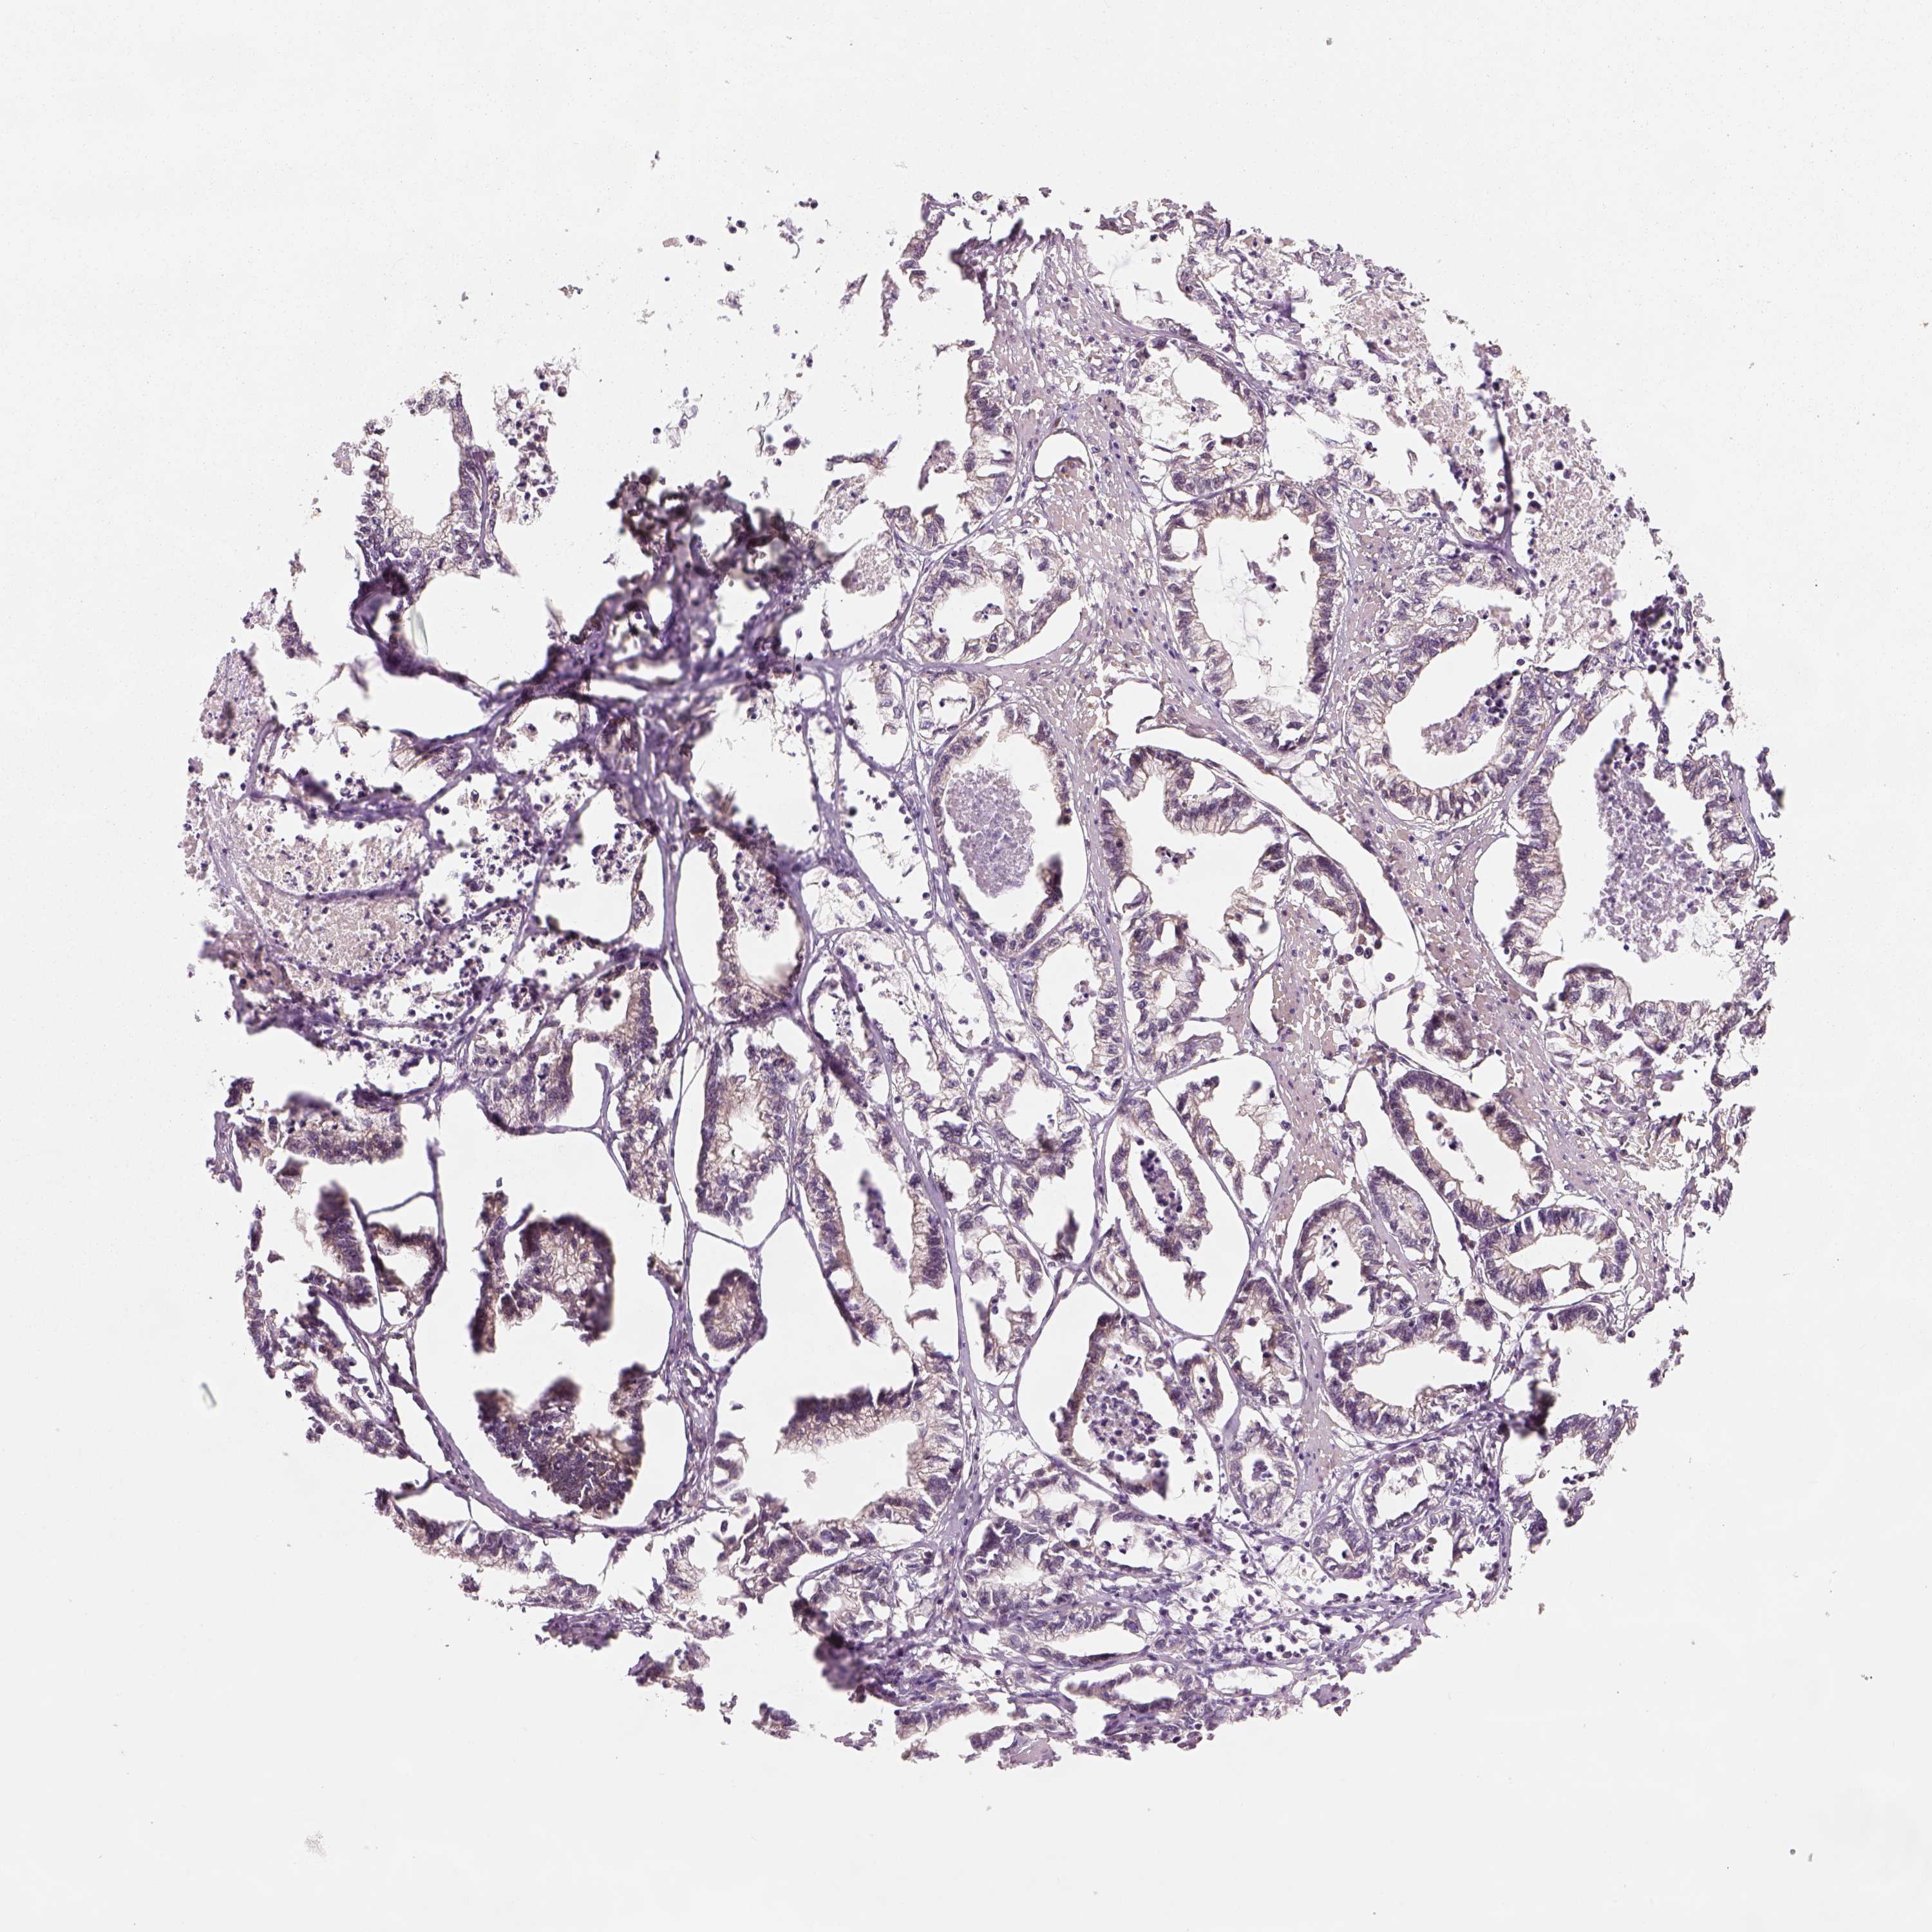

STOMACH CANCER - Protein expressioni

A mouse-over function shows sample information and annotation data. Click on an image to view it in a full screen mode. Samples can be filtered based on level of antibody staining by selecting one or several of the following categories: high, medium, low and not detected. The assay and annotation is described here.

Note that samples used for immunohistochemistry by the Human Protein Atlas do not correspond to samples in the TCGA dataset.

Antibody stainingi

Antibody staining in the annotated cell types in the current human tissue is reported as not detected, low, medium, or high, based on conventional immunohistochemistry profiling in selected tissues. This score is based on the combination of the staining intensity and fraction of stained cells.

Each image is clickable and will lead to virtual microscopy that enables deeper exploration of all samples and also displays staining intensity scores, fraction scores and subcellular localization as well as patient and tissue information for each sample.

Antibody HPA073653

Staining

High

Medium

Low

Not detected

Intensity

Strong

Moderate

Weak

Negative

Quantity

>75%

75%-25%

<25%

None

Location

Nuclear

Cytoplasmic/membranous

Cytoplasmic/membranous,nuclear

Adenocarcinoma, NOS